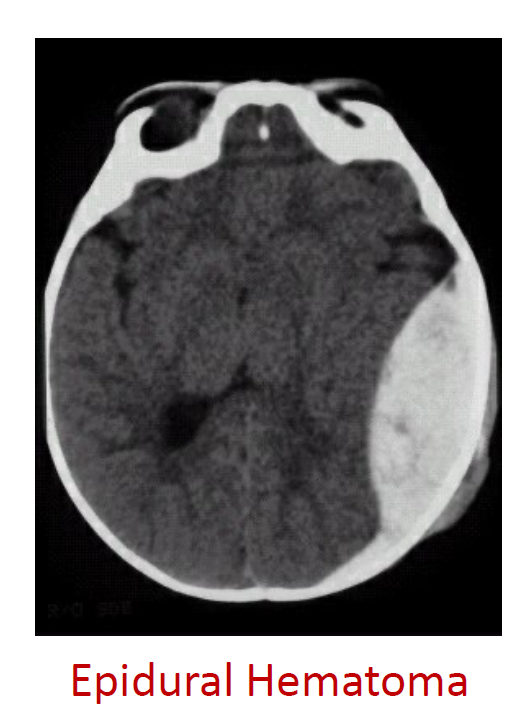

• A fracture of the pterion can tear the middle meningeal artery leading to an epidural hematoma. This is where blood accumulates between the skull and the dura mater causing compression of the brain. Results in a lens-shaped image on MRI.

• Label the type of hematoma

A) epidural hematoma